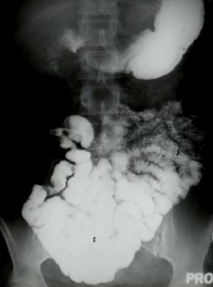

What are the top two causes of this?

1) Adhesions 2) Hernia. Note the dilated loops of bowel indicating small bowel obstruction.